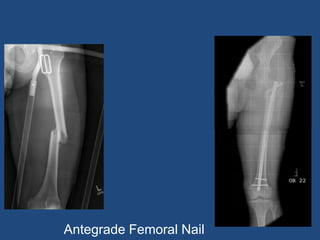

Femoral Intramedullary Nailing

• Antegrade (Through hip)

• Common, and can be used for all shaft fractures

Antegrade Femoral Nail